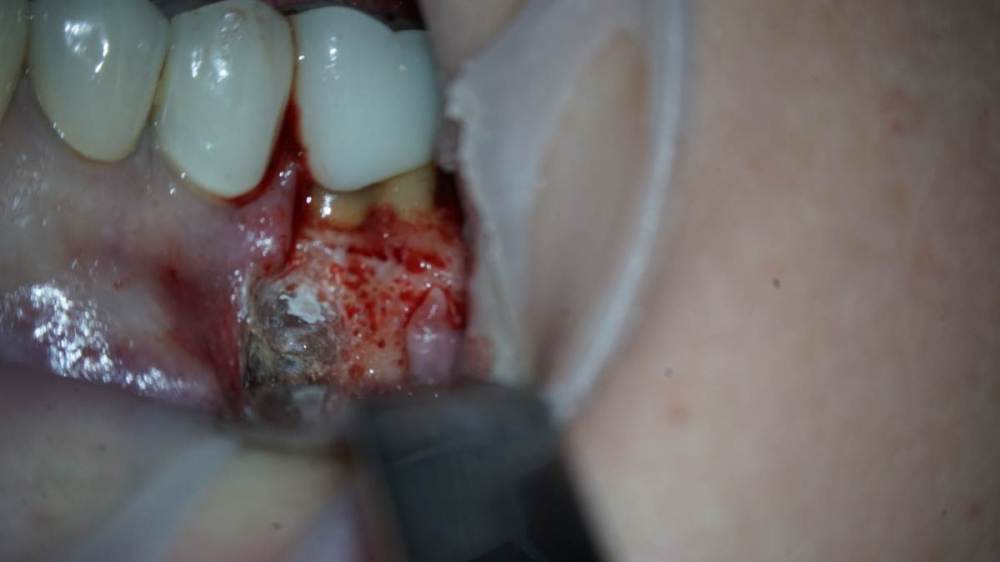

Всем привет!Обострение хронического Pt, ввиду невозможности ортоградной ревизии принято решение об апикальной хирургии.Все манипуляции производятся только под визуальным контролем операционного микроскопа?